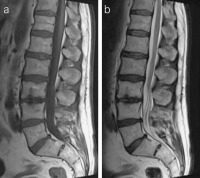

Abbildung 1a-b: MRT 1,5 Tesla, (a) sagittale T1-gewichtete Sequenz nach Kontrastmittelgabe mit Subtraktion sowie (b) T2-gewichtete Sequenz: Kontrastmittelannahme der Wirbelkörper L3/L4 begleitet vom massiven Knochenmarksödem, 2 Wochen vor der X-LIF-Operation.

Abbildung 3: MRT 1,5 Tesla, (a) sagittale T1-gewichtete Sequenz nach Kontrastmittelgabe sowie (b) T2-gewichtete Sequenz: Follow-up-MRT-Bilder ohne Hinweise für Knochenmarksödem bzw. entzündliche Veränderung.